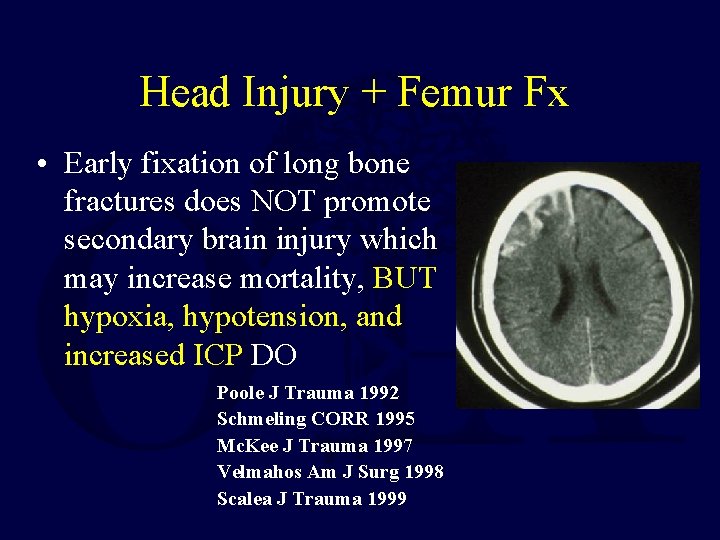

Head Injury + Femur Fx • Early fixation of long bone fractures does NOT promote secondary brain injury which may increase mortality, BUT hypoxia, hypotension, and increased ICP DO Poole J Trauma 1992 Schmeling CORR 1995 Mc. Kee J Trauma 1997 Velmahos Am J Surg 1998 Scalea J Trauma 1999